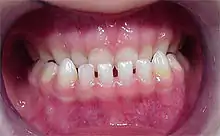

Un diastème (ou diastématie) (du grec διάστημα / diástêma, « intervalle ») est, en odontologie, un écartement entre deux dents normalement adjacentes. Il est plus fréquemment rencontré entre les deux incisives centrales de la mâchoire supérieure. Il peut être congénital ou acquis.

Diastème interincisif

Le diastème entre les incisives supérieures (diastème interincisif) est dû à la présence d'un frein labial (tendon qui attache les lèvres à la mâchoire) trop puissant et qui ne se rétracte pas suffisamment lorsque les dents poussent[1]. Il peut-être dû aussi à une pulsion de la langue lors de la déglutition et/ou de l'articulation.